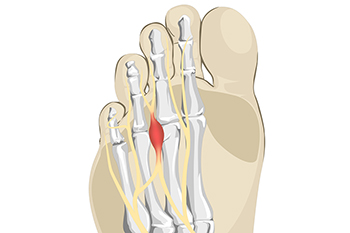

A tailor’s bunion, also known as a bunionette, occurs when the 5th metatarsal bone (the bottom bone on the little toe) begins to shift outwards. Tailor’s bunions are very similar to a normal bunion which occurs on the big toe, but instead, they occur on the pinky toe. A tailor’s bunion will present itself as a swollen bump on the outside of the pinky toe, and it may get larger over time. They can be red and painful, and they tend to get worse as they rub against the shoe. Some of the reasons Tailor’s bunions may form include shoes that don’t fit correctly, an inherited structural foot problem, loose ligaments in the foot, or an inverted foot that leans outwards. Patients who are struggling with a painful Tailor’s bunion should consult with a podiatrist for suggestions on both relieving the pain and treating the bunion.

A tailor’s bunion, also known as a bunionette, occurs when the 5th metatarsal bone (the bottom bone on the little toe) begins to shift outwards. Tailor’s bunions are very similar to a normal bunion which occurs on the big toe, but instead, they occur on the pinky toe. A tailor’s bunion will present itself as a swollen bump on the outside of the pinky toe, and it may get larger over time. They can be red and painful, and they tend to get worse as they rub against the shoe. Some of the reasons Tailor’s bunions may form include shoes that don’t fit correctly, an inherited structural foot problem, loose ligaments in the foot, or an inverted foot that leans outwards. Patients who are struggling with a painful Tailor’s bunion should consult with a podiatrist for suggestions on both relieving the pain and treating the bunion.